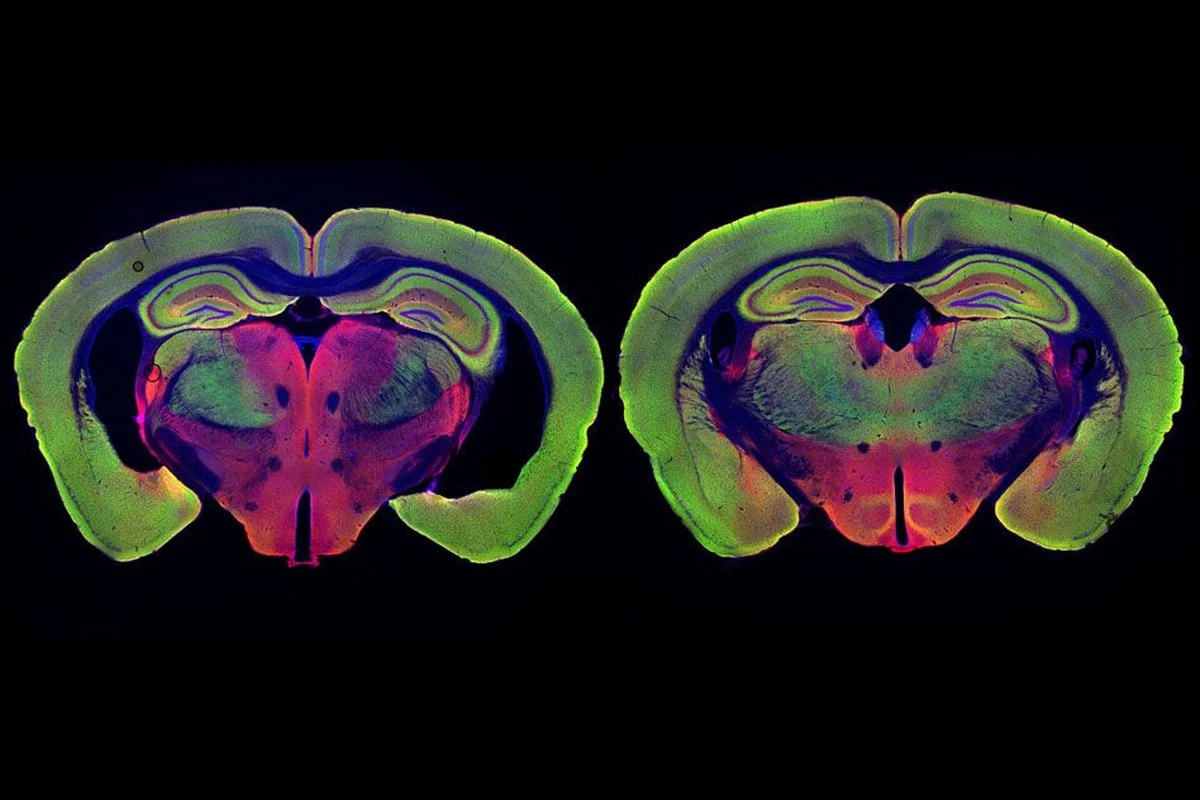

And now for the most interesting part. Při testech na myších modelech se ukázalo, že FLAV-27 neudělal jen kosmetické změny. Zvířata s pokročilou formou nemoci se začala chovat jako jejich zdraví vrstevníci. Zlepšila se jim paměť, sociální interakce a obnovila se funkce synapsí – tedy spojů, kterými si mozkové buňky posílají informace.

Mnoho lidí přehlíží, že Alzheimer není jen o ztrátě jména, ale o celkovém „zhasínání“ mozku. Tato nová látka dokázala u pokusných organismů prodloužit život a dokonce nakopnout mitochondrie, což jsou takové malé elektrárny uvnitř našich buněk.